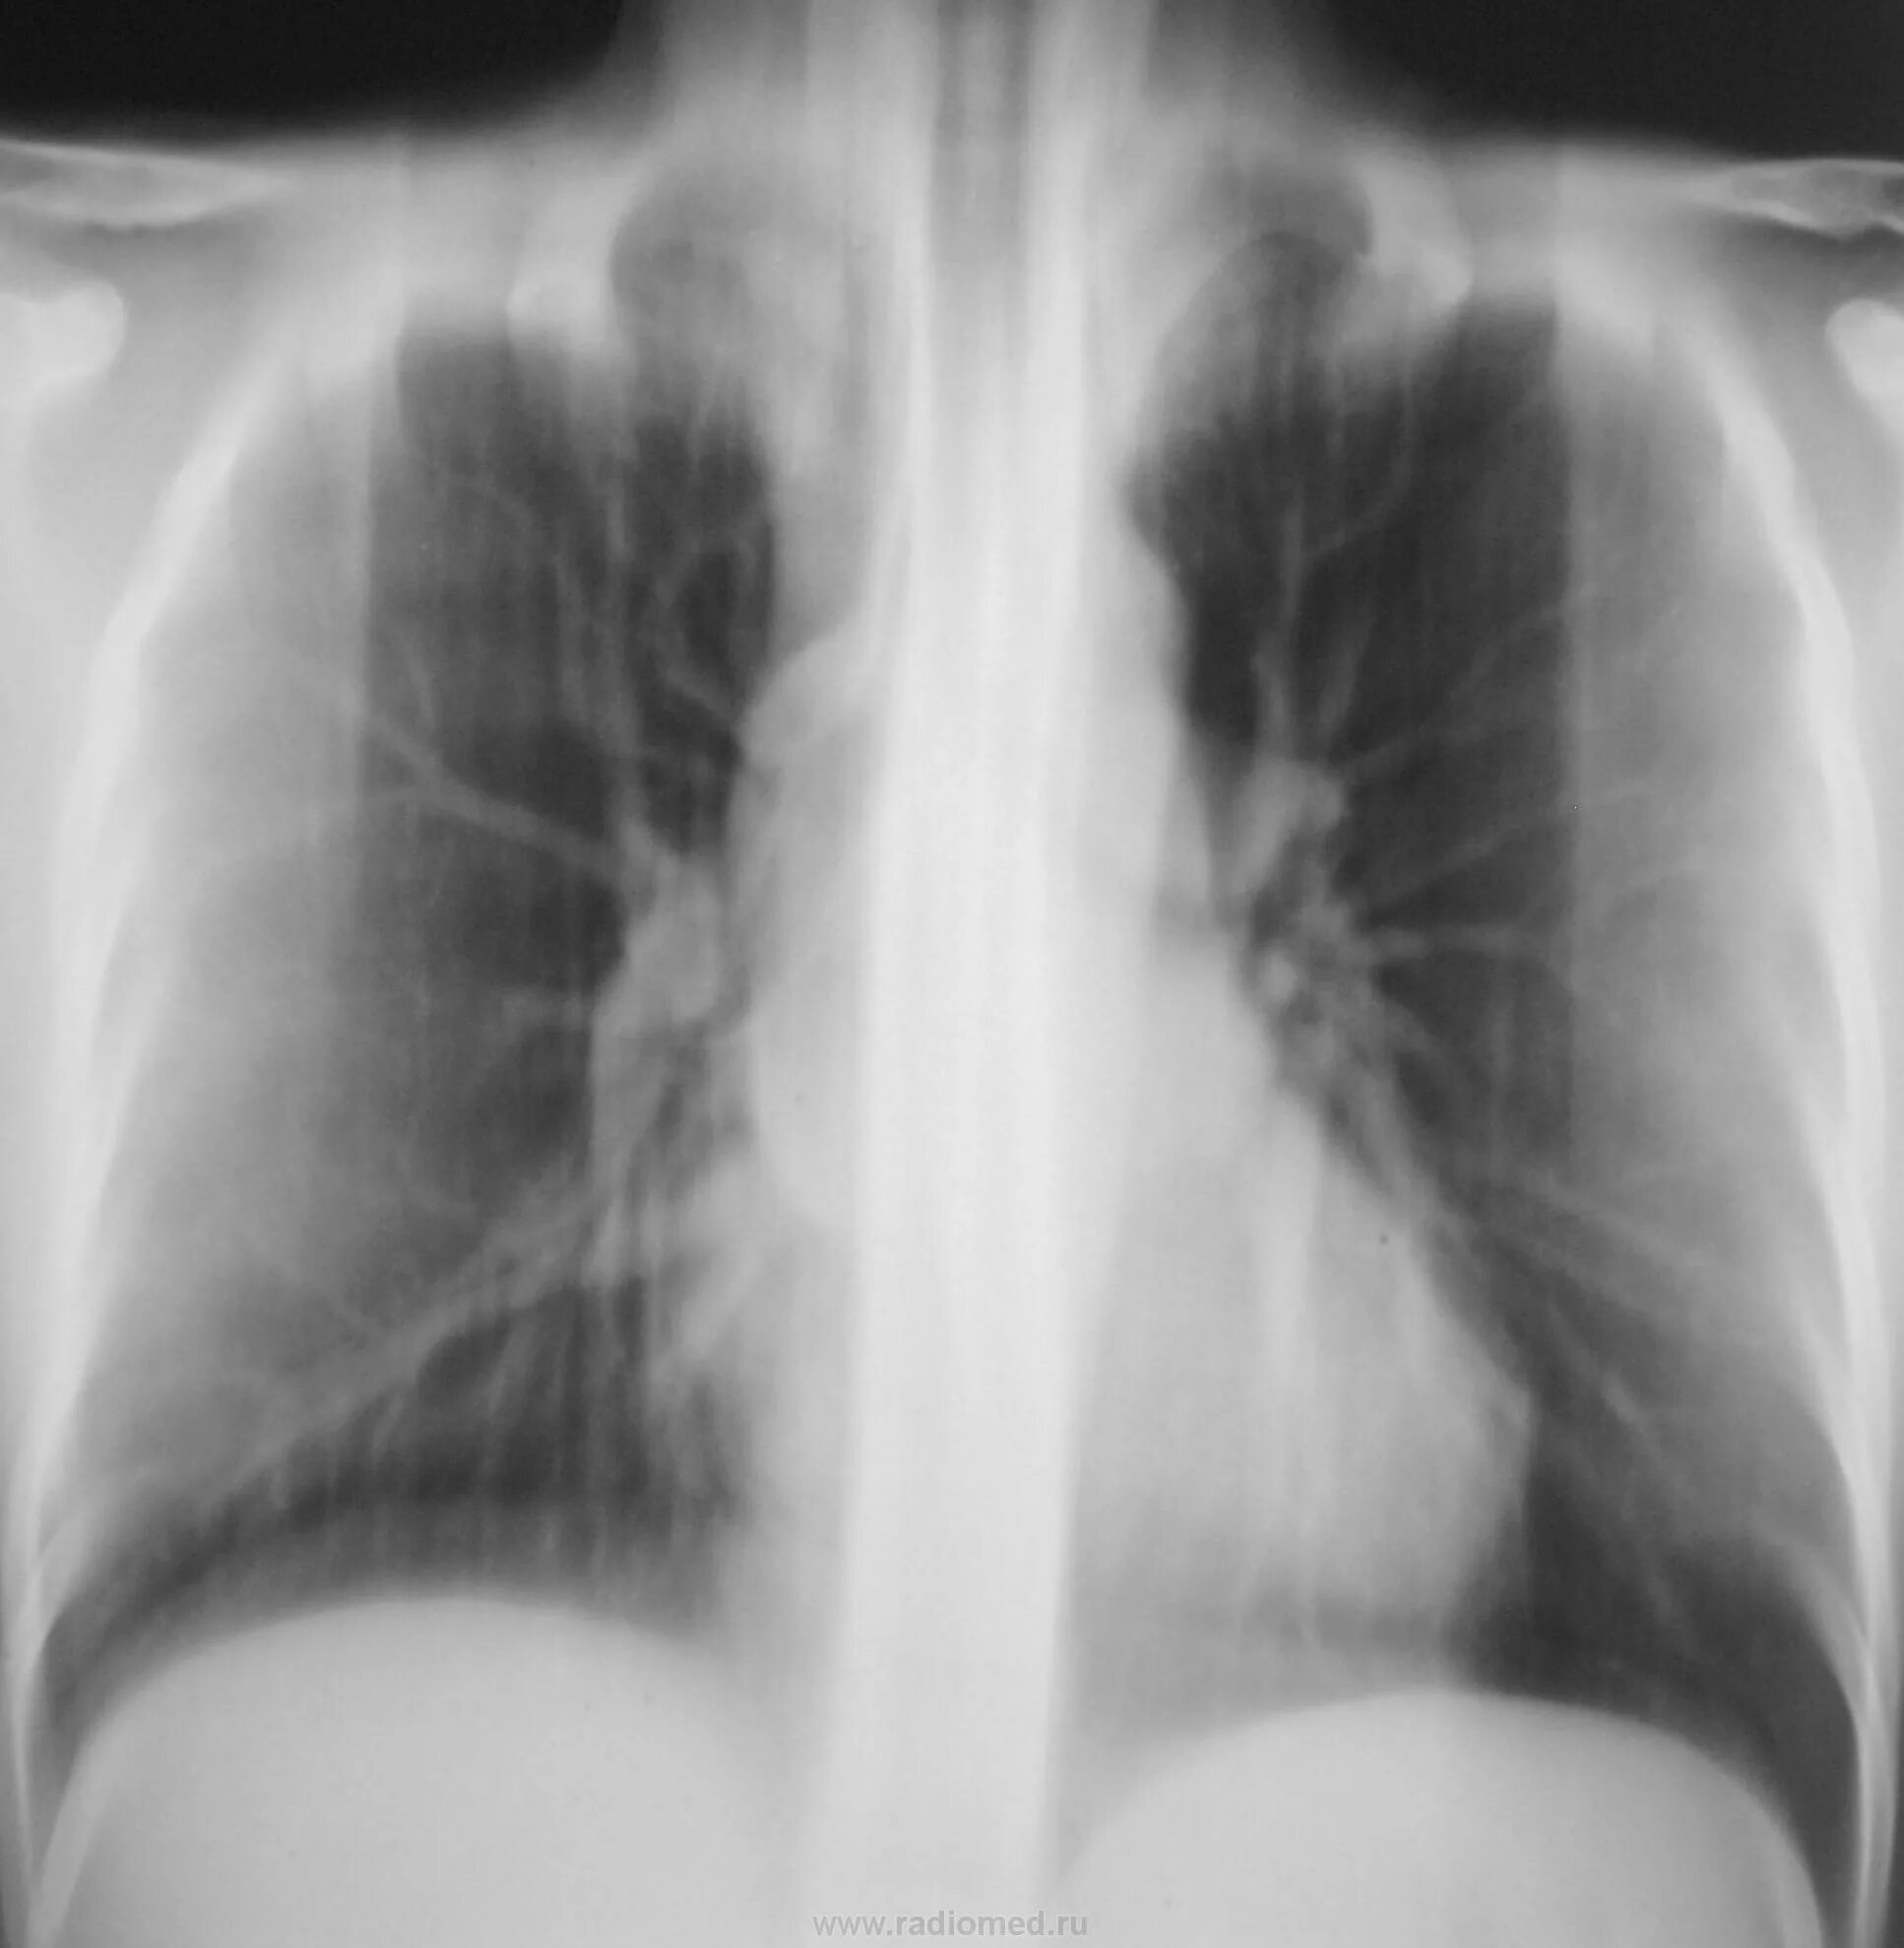

Что значит аорта уплотнена на флюорографии